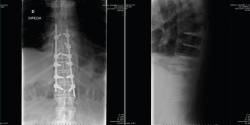

En la Figura 1 se muestra la primera radiografía que le realizan en el centro hospitalario más cercano al accidente. En ella visualizamos un perfil dorsolumbar realizado sobre la camilla de transporte con 2 imágenes. Por un lado, una apertura anterior patológica a través de disco a nivel dorsal, concretamente T10/T11. También observamos una sindesmofitosis de todo el raquis que conocemos como “caña de bambú”. Esto orienta a una enfermedad reumática, concretamente una espondiloartitis anquilosante(1).

Figura 1. Radiografía inicial.